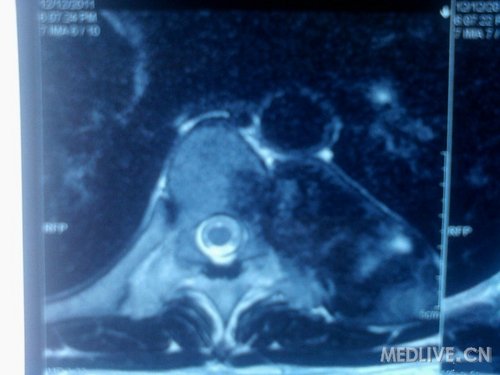

患者 男 42岁 自觉胸背部不适10个月,入院,ct见图 查体未见特殊体征,未及包快,无压痛,四肢肌力正常。血常规、凝血、肝肾功能正常,碱性磷酸酶 81(正常参考值范围)

定为在左第七肋骨处(11.28)

患者是12月7号入院的,请骨科会诊后,12月12日做了核磁,期间患者主诉均轻